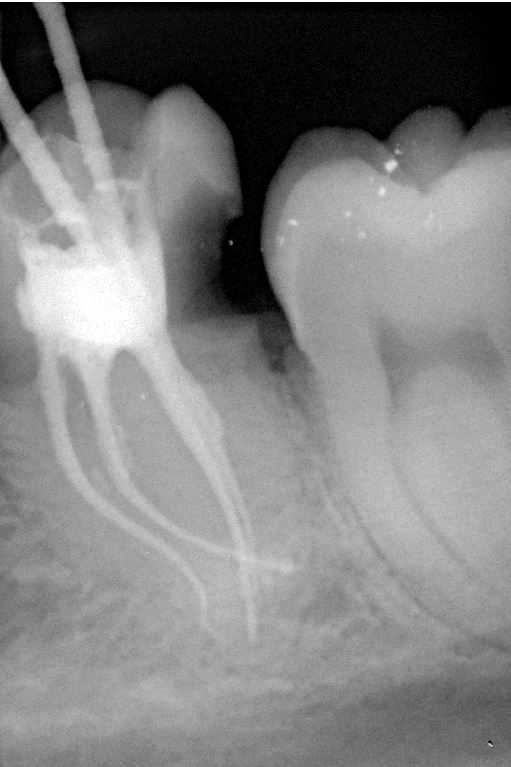

Unter örtlicher Betäubung ist die Behandlung in der Regel schmerzfrei. Nach Entfernung der Karies und nach der Schaffung eines Zugangs in den Zahn werden die Kanaleingänge dargestellt und die Länge jedes einzelnen Kanals wird möglichst exakt unter Anwendung von Röntgen ausgemessen. Abhängig vom zu behandelten Zahn kann die Anzahl der Kanäle stark variieren.

Mit Hilfe der elektronischen Längenmessung und digitalen Röntgenbildern können die Länge und Krümmung der Kanäle bestimmt und der Verlauf beurteilt werden.

Da die Wurzelkanäle sehr klein sind und sich oft verzweigen, ist es nicht immer einfach, alle Kanäle mit ihren Seitenästen aufzufinden.

Bei der modernen endodontischen Behandlung können durch ein Dentalmikroskop auch kleinere Kanälchen aufbereitet werden, die man auch mit einer Lupenbrille nicht finden würde.

Nur wenn das Wurzelkanalsystem komplett aufgefunden und gereinigt wird, hat eine Wurzelkanalfüllung eine gute Langzeitprognose.

Fallbeispiel für einen Seitenrand

Fallbeispiel für einen komplexen Kanalverlauf